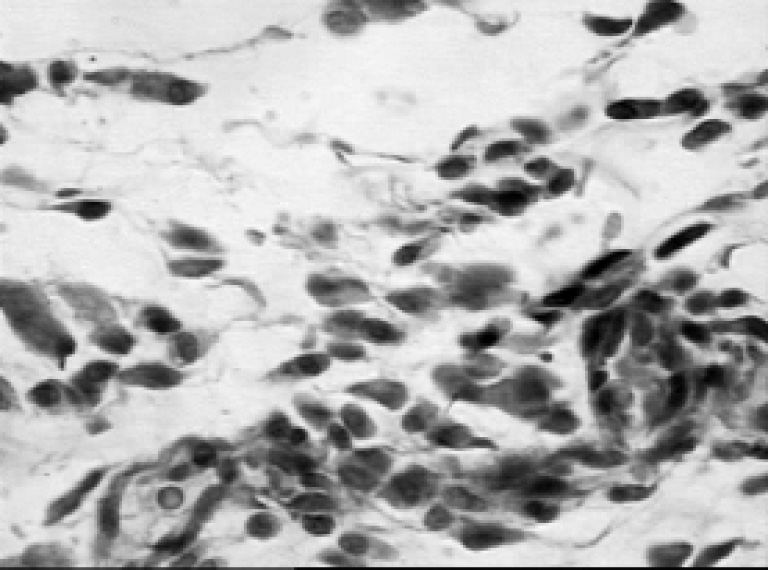

Молодая соединительная ткань была представлена активированными фибробластами, увеличенными в размерах и приобретающими отростчатую форму. Максимальную толщину и развитие грануляционная ткань приобретала в зонах прохождения магистральных сосудов мышц и кожи. Через 10 суток после травмы дефект был покрыт струпом, толщина которого достигала 2–3 мм, на отдельных участках раны отмечали начальные признаки отторжения струпа, преимущественно по краю.

Под струпом формировался слой грануляций, в некоторых местах он распространялся на всю глубину раны. Грануляционный слой, непосредственно прилегающий к некротической зоне, состоял из 5–7 рядов крупных, горизонтально расположенных фибробластов. Подлежащие слои были представлены рыхлой соединительной тканью, в которой прослеживались в значительном количестве вертикальные тонкостенные капилляры. В участках отторжения струпа нарастающий эпителий по краям раны располагался на подложке из растущей соединительной ткани (рис. 4). Отмечались выраженная клеточная инфильтрация, большое количество кровеносных сосудов и активированных фибробластов в грануляциях дна раны.

Рис. 4. Микропрепарат мягких тканей в области раны бедра крысы через 10 суток после РМП. Окраска гематоксилином и эозином, ув. ×250